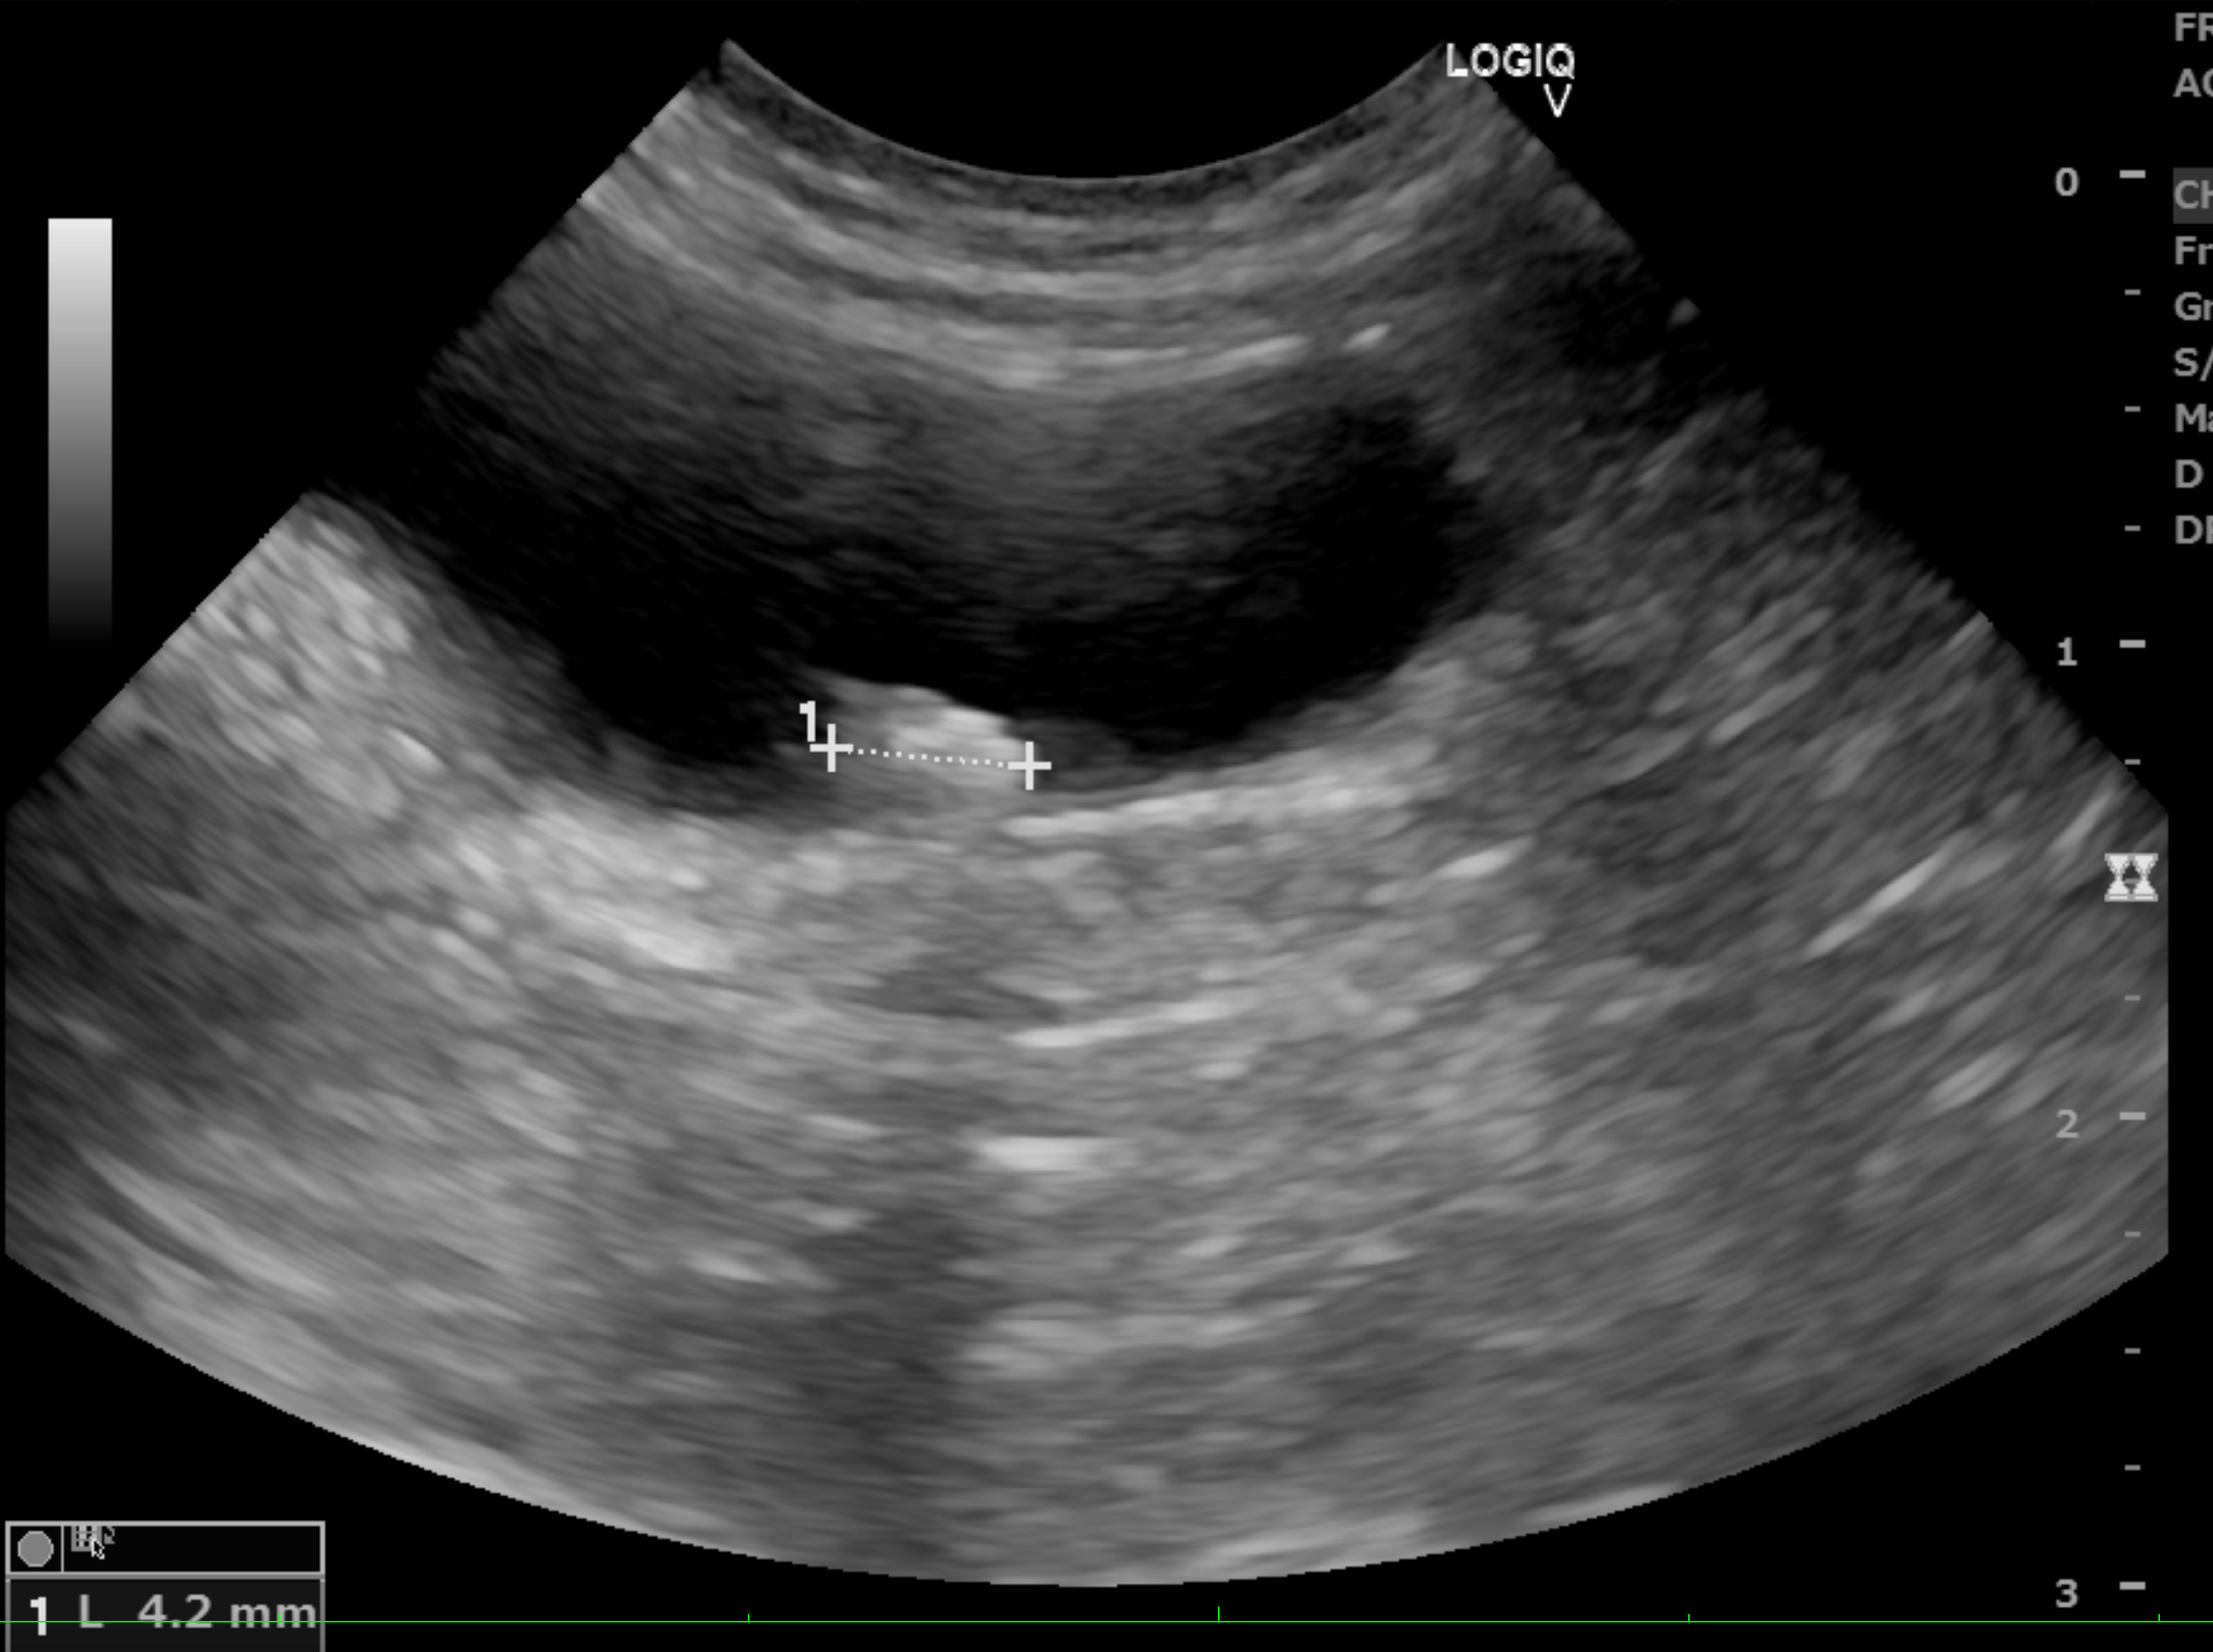

<膀胱のエコー画像>

膀胱内に結石が認められる